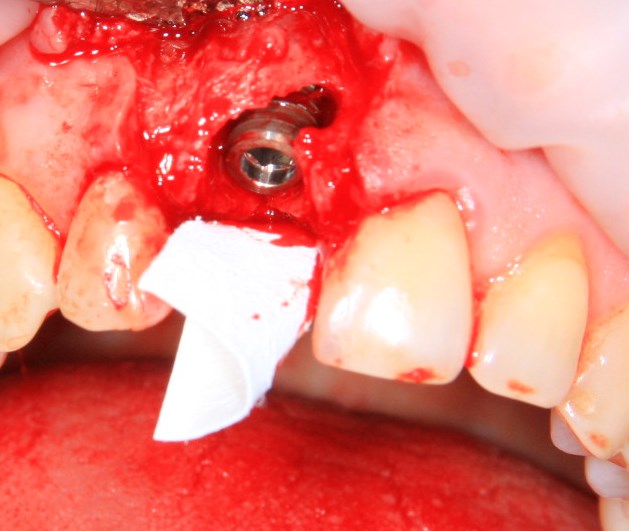

Немедленная имплантация — оптимальное решение в любой клинической ситуации